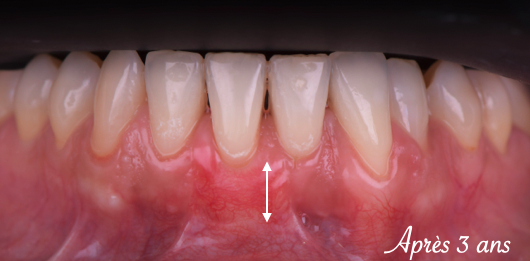

Traitement des récessions gingivales des incisives mandibulaires

Description détaillée du lambeau déplacé coronairement associé à un greff on de tissu conjonctif Le traitement des récessions gingivales dans le secteur antérieur mandibulaire s’avère

Les racines sont alors recouvertes, redonnant à la patiente un sourire harmonieux.

Une fois le recouvrement des racines terminé, la sensibilité dentaire disparait.

Le recouvrement de la racine a été obtenu par une technique de lambeau déplacé coronairement, qui consiste à déplacer la gencive du bas vers le haut.

Un greffon prélevé au palais a également été ajouté en dessous pour épaissir la gencive et la rendre plus résistante dans le temps.